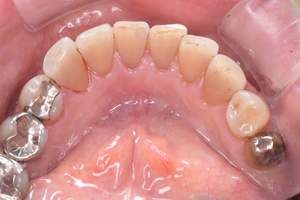

治療前 1

治療後 1

治療前 2

治療後 2

治療前 3

治療後 3

| 年齢 | 58歳・女性 |

|---|---|

| 主訴 | 前歯の着色除去希望 |

| 治療内容 | エアフロー |

| 費用 | 合計:5,500円 (2024年8月現在) |

| 治療期間 | 60分 |

| リスク・副作用 | 呼吸器疾患のある方や放射線治療を行っている方、ナトリウム摂取制限を必要とする方や妊娠中の方は処置を受けられないことがあります。 施術を受ける際、舌や歯肉に当たった粒子でチクチクとした痛みを感じることがあります。 |

| 治療方針 | 歯周病と虫歯の治療を担当医と相談し進めていく予定です。 |

| 担当者所見 | 約4年ぶりの来院でした。他の歯医者に行っても満足いくクリーニングをしてもらえず悩んでいる様子でした。問診時には手で口元を隠すようにお話されていましたが、エアフロー後は笑顔でお話するようになっていました。 |